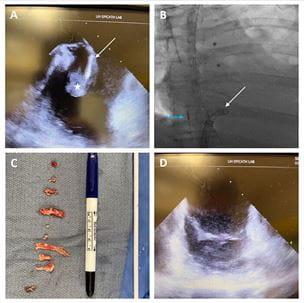

University Hospitals Harrington Heart & Vascular Institute First in U.S. to Report New Minimally Invasive Approach to Treat Infective Endocarditis

New strategy could revolutionize care for difficult-to-treat patients - Innovations in Cardiovascular Medicine & Surgery | Fall 2021